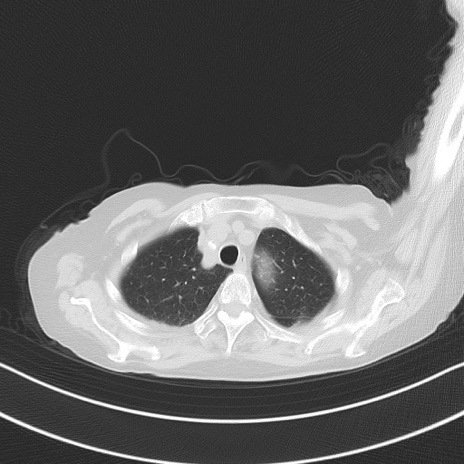

横断像

他院CT